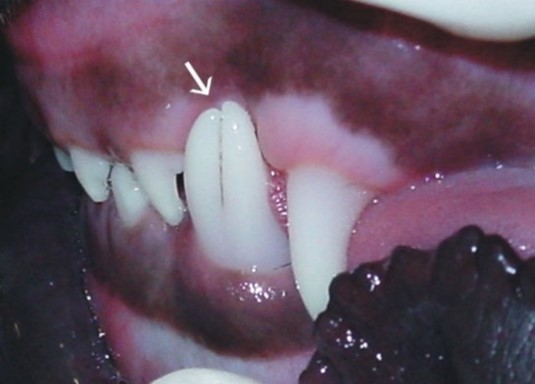

aus: Developmental Structural Tooth Defects in Dogs - Experience From Veterinary Dental Referral Practice and Review of the Literature. Boy S, Crossley D, Steenkamp G. Front Vet Sci. 2016 Feb 8;3:9. doi: 10.3389/fvets.2016.00009. eCollection 2016. Review.)

Zwillingszahn aus einem Zahnkeim

(aus: Developmental Structural Tooth Defects in Dogs - Experience From Veterinary Dental Referral Practice and Review of the Literature. Boy S, Crossley D, Steenkamp G. Front Vet Sci. 2016 Feb 8;3:9. doi: 10.3389/fvets.2016.00009. eCollection 2016. Review.)